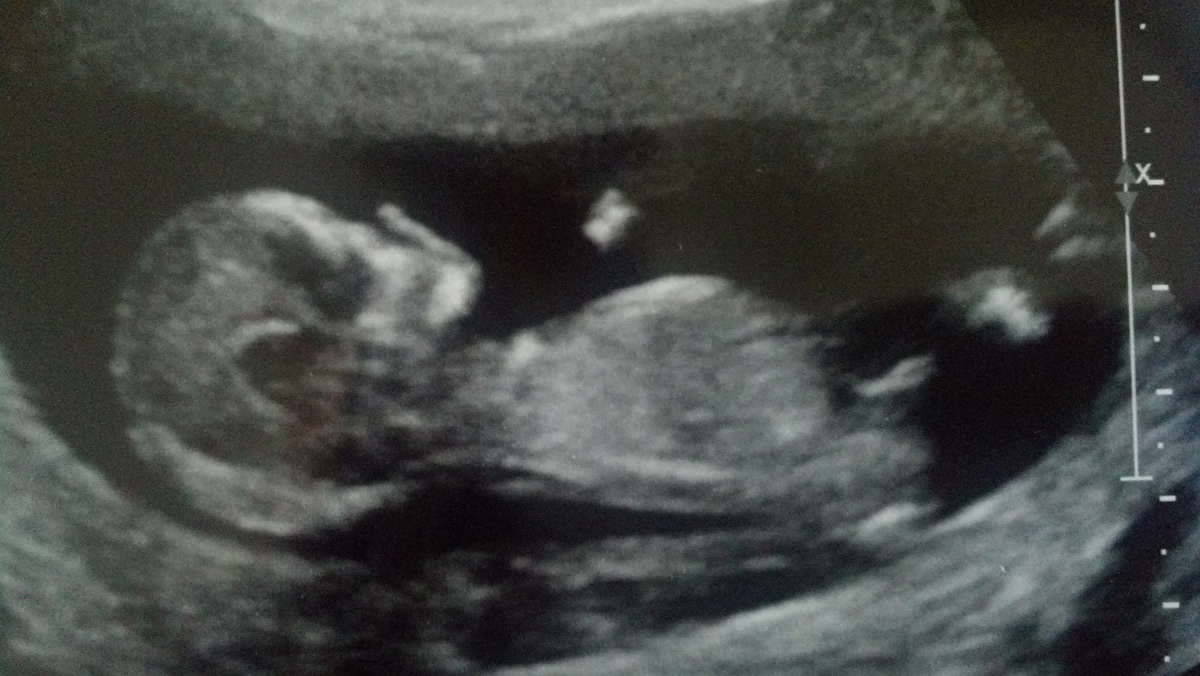

This was taken at 13 weeks exactly. I have posted on another board and I would like to get more guesses. I don't get my anatomy scan until Jan. 3rd and it's hard wait!

Attachment 7235

Super tricky..the nub seems to be pointing up but skull looks girly..I'm going with girl.

shape girl, angle boy so unsure - do you have any more pics in case its just a bad photo

Forks can be seen on both boy and girl nubs. It doesn't look tricky to me as it is clearly angled up. 2nd pic has a textbook boy nub. Congrats!